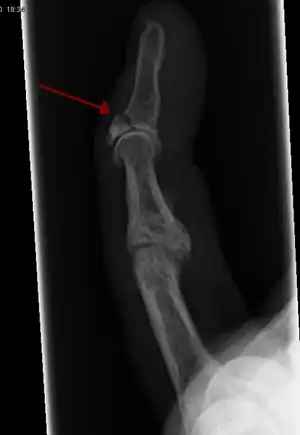

X-ray showing fracture at the insertion of the extensor tendon